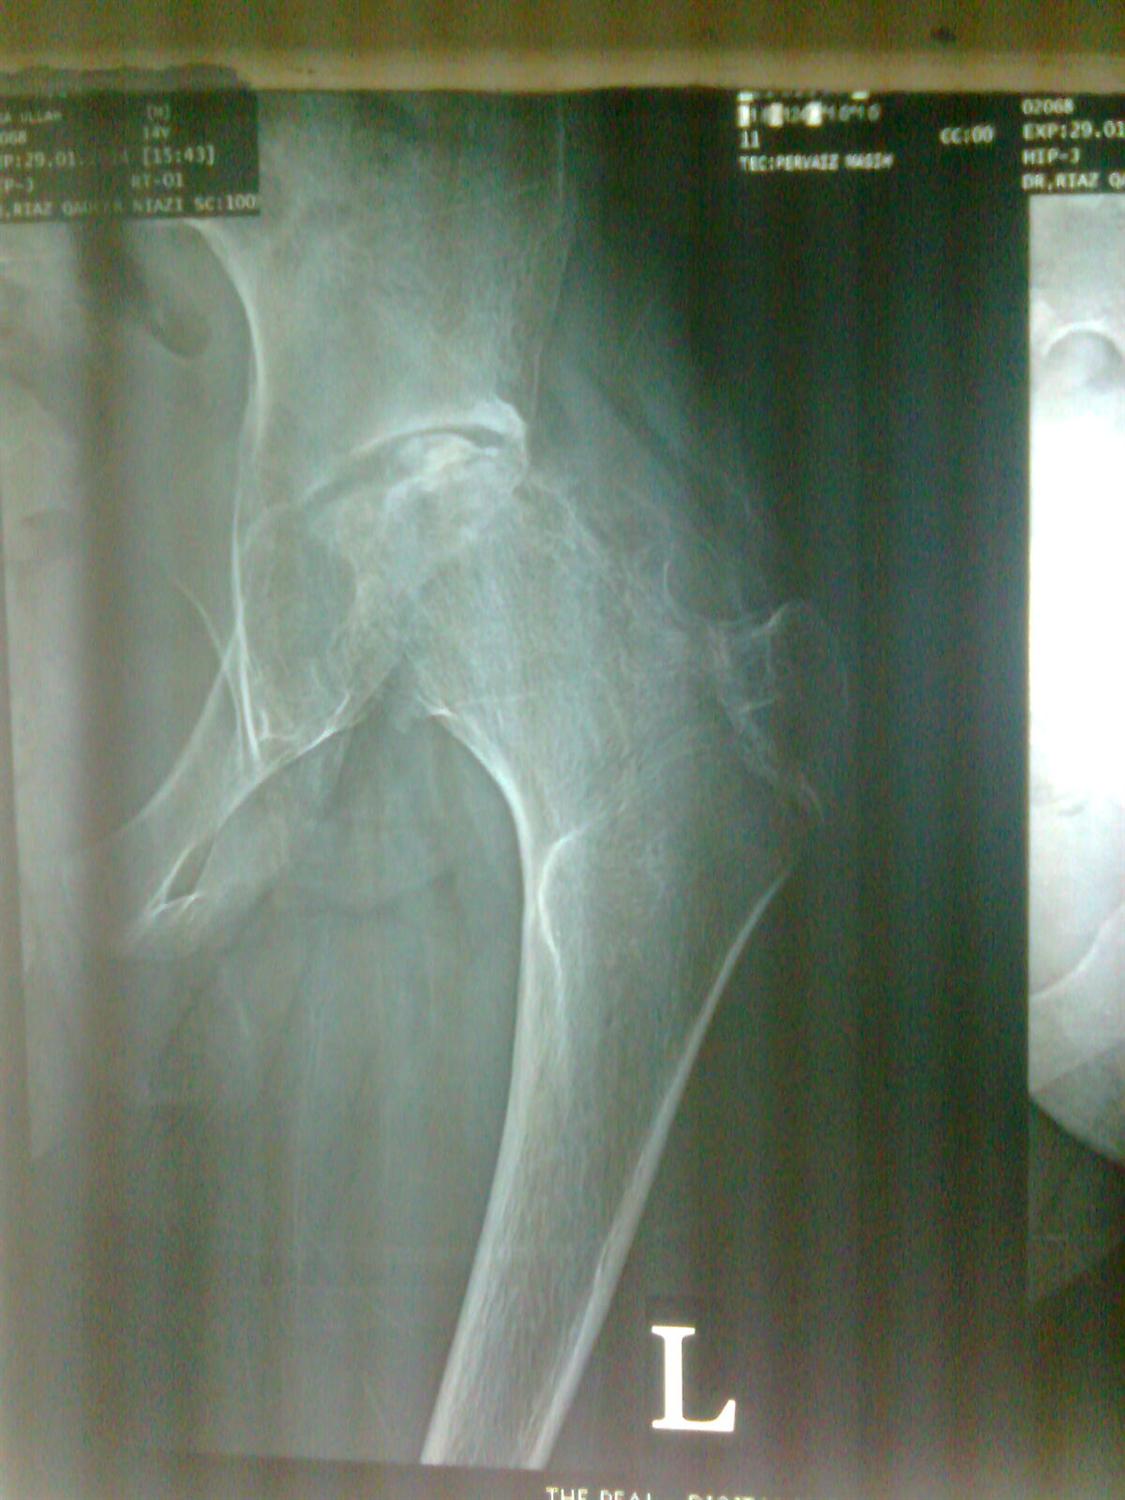

Hip Septic Arthritis Pediatric Pediatrics Septic Arthritis Pediatrics septic arthritis is an infection in the joint fluid (synovial fluid) and joint tissues. Septic arthritis affects children of all ages; — septic arthritis of the pediatric hip joint (sah) is a rare but serious orthopedic emergency requiring. — the term septic arthritis usually refers to bacterial arthritis or fungal arthritis, but bacterial joint infections are. . Septic Arthritis Pediatrics.

Hip Septic Arthritis Pediatric Pediatrics Orthobullets Septic Arthritis Pediatrics septic arthritis is an infection in the joint fluid (synovial fluid) and joint tissues. — paediatric septic arthritis can be treated by arthrocentesis (articular needle aspiration) with or without irrigation,. — septic arthritis of the pediatric hip joint (sah) is a rare but serious orthopedic emergency requiring. It occurs more often in children than adults. —. Septic Arthritis Pediatrics.

Hip Septic Arthritis Pediatric Pediatrics Orthobullets Septic Arthritis Pediatrics septic arthritis is an infection in the joint fluid (synovial fluid) and joint tissues. — septic arthritis is a surgical emergency. — paediatric septic arthritis can be treated by arthrocentesis (articular needle aspiration) with or without irrigation,. — the term septic arthritis usually refers to bacterial arthritis or fungal arthritis, but bacterial joint infections are. Septic. Septic Arthritis Pediatrics.

Pediatric Septic Hip Arthritis What You Need to Know Septic Arthritis Pediatrics in most children, septic arthritis only affects one joint in the body. — septic arthritis is a surgical emergency. — septic arthritis of the pediatric hip joint (sah) is a rare but serious orthopedic emergency requiring. The most common sites for septic arthritis include the: septic arthritis is an infection in the joint fluid (synovial fluid). Septic Arthritis Pediatrics.